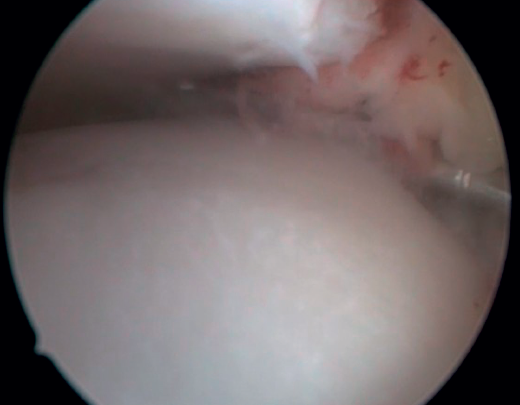

Bassett's ligament should be preserved as long as it does not have a pathological appearance, ruling out thickening, partial tears or reciprocal lesions on the anterolateral surface of the talus (Figure 6), which are associated with anterolateral or rotational instabilities. The peroneal insertion is used as a reference to locate the distal insertion of the ATFL. The deltoid ligament at the medial groove should be inspected if associated rotational instability is suspected. During arthroscopy, direct ligament repair can be performed using sutures and anchors.

Figure 6. Groove produced by friction of the talar dome against Bassett's ligament, visible after resection of the latter. The ligament presented a partial tear and scar thickening.